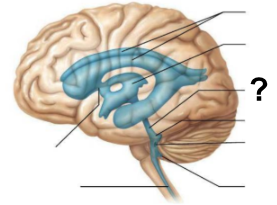

After the third ventricle, CSF flows through which narrow passage, labeled “?”, to reach the fourth ventricle?

Cerebral aqueduct